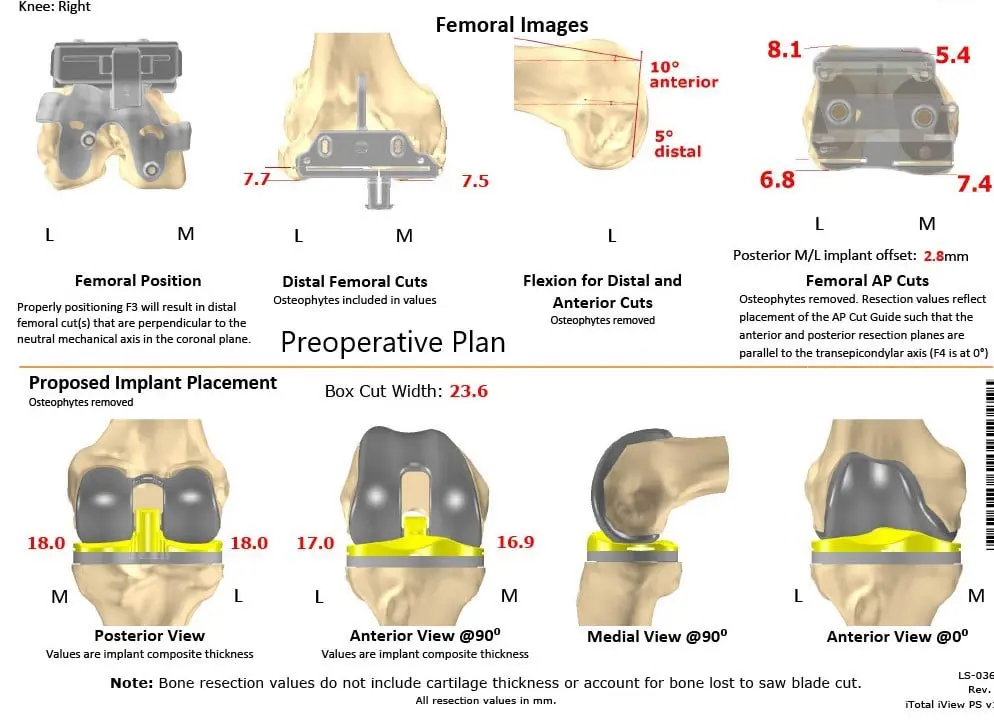

A preoperative CT scan obtained a few weeks prior to the procedure. The data was used to assess the patient’s unique anatomy and biomechanics. Customized unique patient-specific implants were made. Disposable bone cutting guides were 3D constructed to match the patient’s anatomy. A preoperative plan was formulated to guide the surgery.

Complete Orthopedics patient-specific surgical plan for a custom right total knee replacement in a 55-year-old female with Prior ACL Reconstruction.

Complete Orthopedics patient specific surgical plan for a custom right total knee replacement in a 55-year-old female with prior ACL Reconstruction (scan 2)